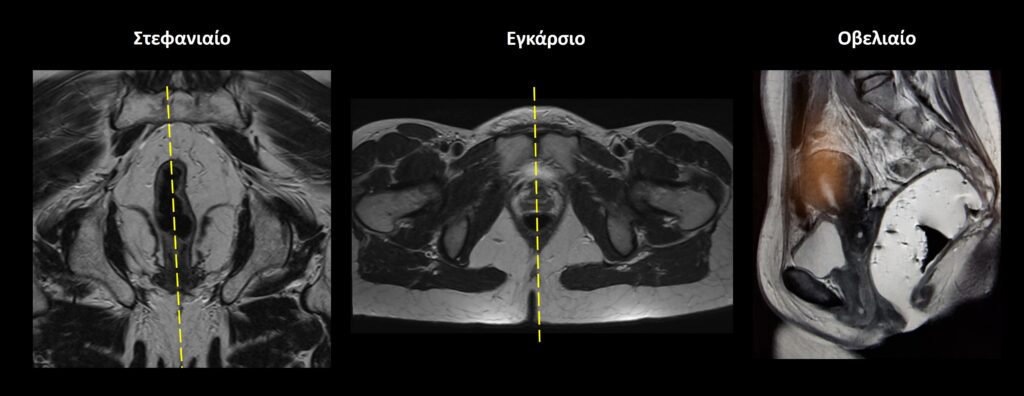

• Για την στατική απεικόνιση προτείνεται η χρήση ακολουθιών υψηλής ανάλυσης βάρους T2(π.χ. TurboSpinEcho/TSE, FastSpinEcho/FSE) και στα 3 επίπεδα οβελιαίο, εγκάρσιο, στεφανιαίο)

Σχεδιασμός τομών Στατικές Ακολουθίες

Οβελιαίο επίπεδο (Sagittal): οι οβελιαίες τομές σχεδιάζονται κατά μήκος των οργάνων της πυέλου τόσο στο εγκάρσιο όσο και στο στεφανιαίο επίπεδο. Η κλίση των τομών στο εγκάρσιο επίπεδο πρέπει να είναι παράλληλη με τη νοητή γραμμή που ενώνει την ηβική σύμφυση με τον πρωκτικό σωλήνα. Κατάλληλη κλίση πρέπει να δοθεί και στο στεφανιαίο επίπεδο, παράλληλα με το ορθό και τον πρωκτικό σωλήνα. Οι τομές πρέπει να περιλαμβάνουν τα όργανα της πυέλου, από την δεξιά έως την αριστερή κοτύλη.

Εγκάρσιο (Axial/Transversal): οι εγκάρσιες τομές σχεδιάζονται παράλληλα με τις κεφαλές των μηριαίων στο στεφανιαίο επίπεδο και κάθετα στονπρωκτικό σωλήνα στο οβελιαίο επίπεδο. Οι τομές πρέπει να περιλαμβάνουν τα όργανα της πυέλου, από τις λαγόνιες ακρολοφίες (πάνω) έως τον πρωκτό (κάτω).